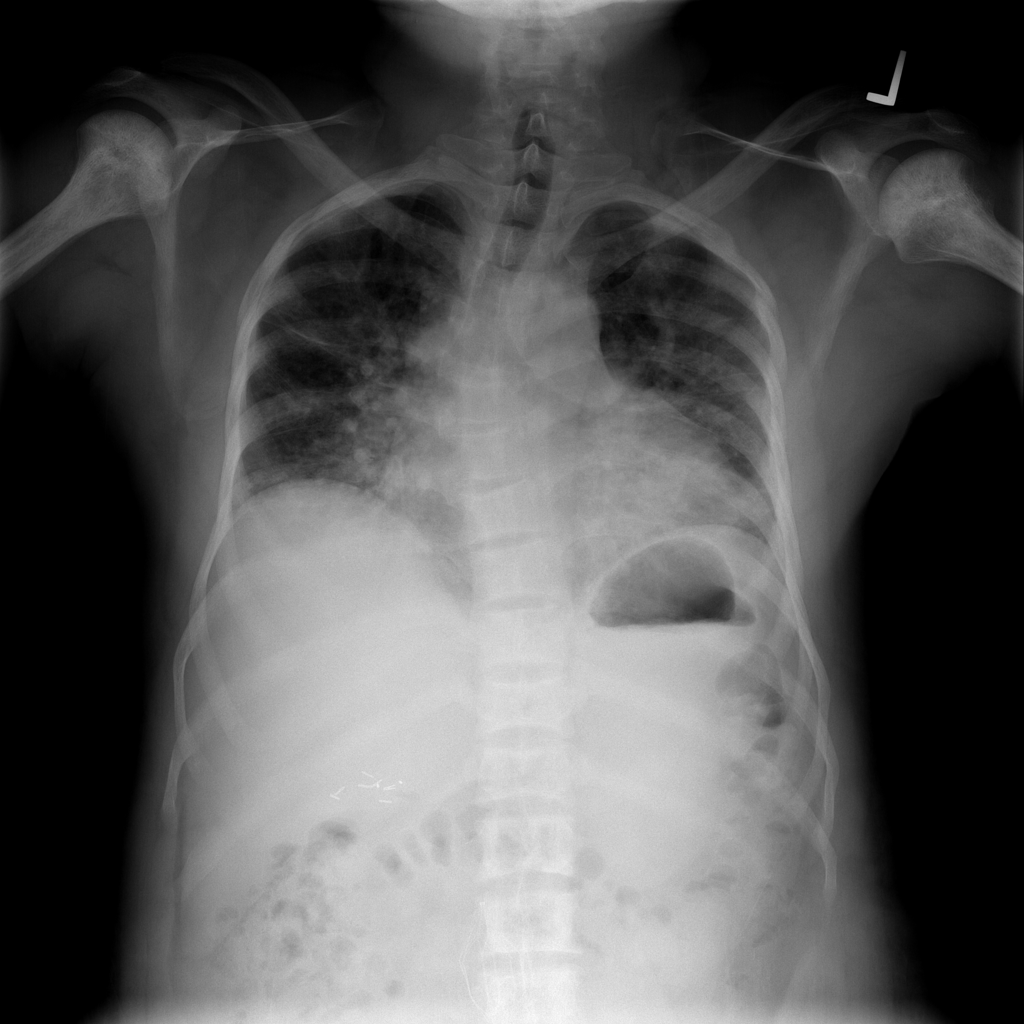

Cardiomegaly

Cardiomegaly means the heart appears enlarged on the chest X-ray. It is a descriptive imaging finding that can be related to heart strain, chronic pressure or volume changes, or even projection effects.

Showing up to 90 reference images for Cardiomegaly.

PAT-4639 · IMG-045Cardiomegaly

PAT-4639 · IMG-045

PA